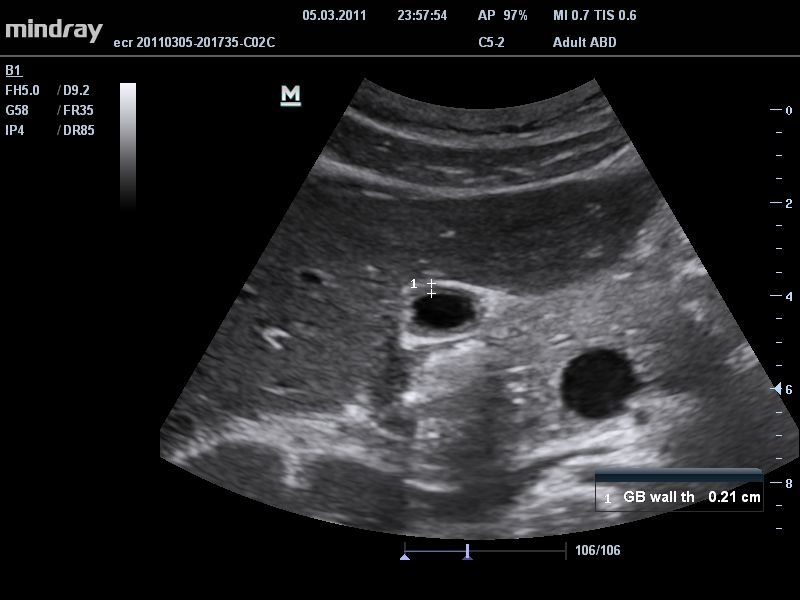

• Микроконвексный датчик Mindray 6C2